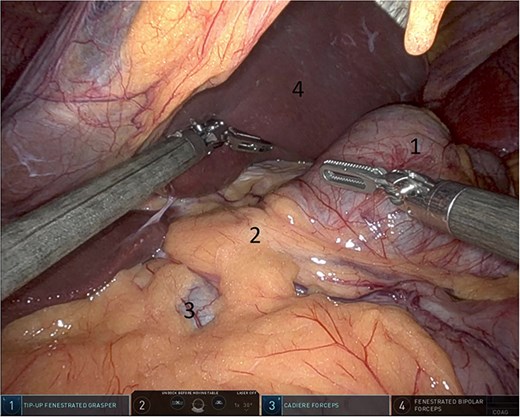

Upon entering the abdominal cavity, dilated bowel loops were observed (Fig. 2), and a significant portion of the colon was found herniated through the foramen of Winslow (Fig. 3). The herniated colon was covered by the pars flaccida (Fig. 4) (Video S1). Careful dissection was performed anterior to the hepatoduodenal ligament (Fig. 5). The gall bladder was retracted to the patient's right upper quadrant, which allowed for the retraction of the foramen of Winslow (Fig. 6) (Video S1). After carefully placing the tip of the instrument posterior to the portal vein and gently elevating it, the herniated colon was successfully reduced (Fig. 7) (Video S1).

Herniated colon through the foramen of Winslow (1: incarcerated colon, 2: hepato-duodenal ligament, 3: herniating colon, 4: the liver).

Pars flaccida covering the herniated bowel (1: pars flaccida over the herniated bowel, 2: the stomach, 3: transverse colon).